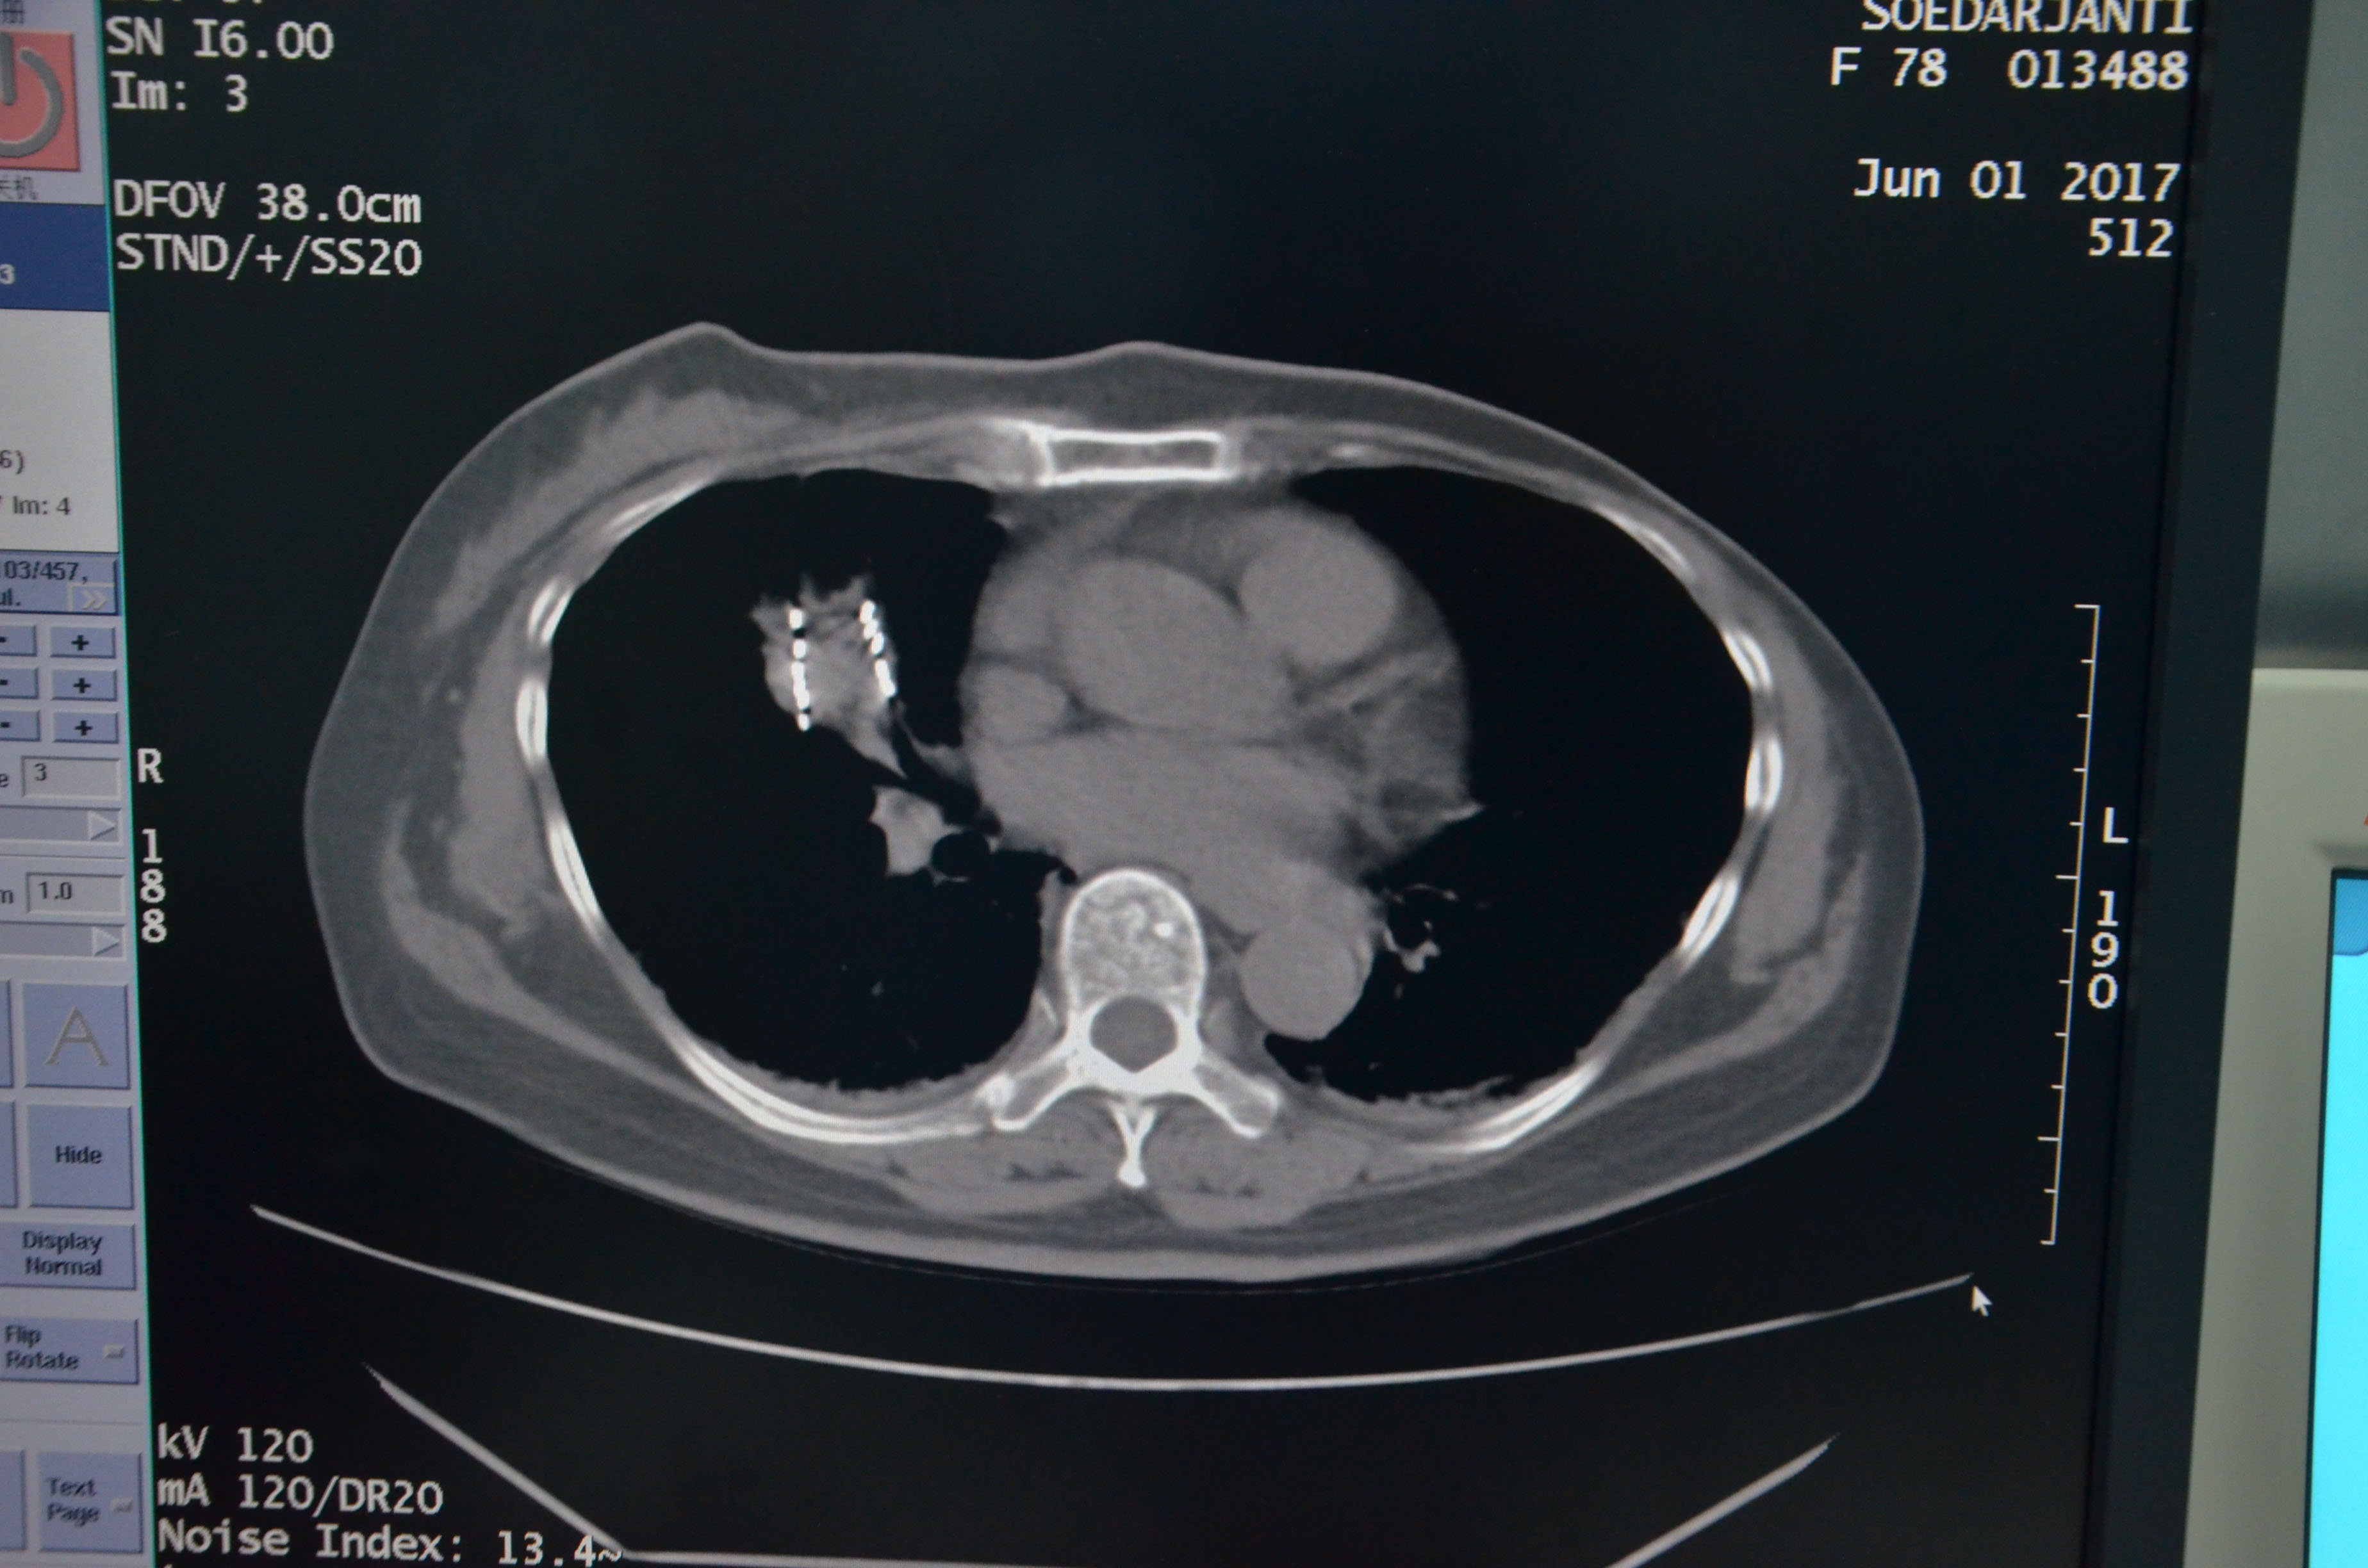

患者女性,今年78岁,来自印尼,5月下旬因左下肢、右胸有明显疼痛而来到广州圣丹福肿瘤医院。经CT检查发现,患者右肺有一个3cm大小肿瘤,伴左股骨转移,经穿刺活检确认为右肺癌Ⅳ期。经医院MDT团队讨论研究,决定为其采取3D微创导向模板引导下的I125粒子植入术。I125粒子持续低剂量组织内照射,局部肿瘤高剂量、周围正常组织低剂量,操作易行,并发症少等特点,对该患者更为适合。

术前患者进行了CT检查,利用CT进行3D建模,通过PROWESS TPS软件(粒子植入治疗计划系统)将患者肿瘤CT扫描图像进行三维重建,完整地呈现出患者皮肤、骨骼、血管和肿瘤之间的关系。设计出每一根穿刺针的进针路径、进针深度、粒子分布及粒子数量、肿瘤受辐射的剂量,最后通过3D打印设备制作出贴合患者皮肤的3D微创导向模板。

6月1日,医院成功为该患者实施3D微创导向模板引导下的I 125粒子植入,术后患者身体状况良好,病情控制稳定。对粒子的分布作出剂量分析,完全符合术前的组织计划剂量。

▲术后粒子分布,与术前组织计划剂量吻合